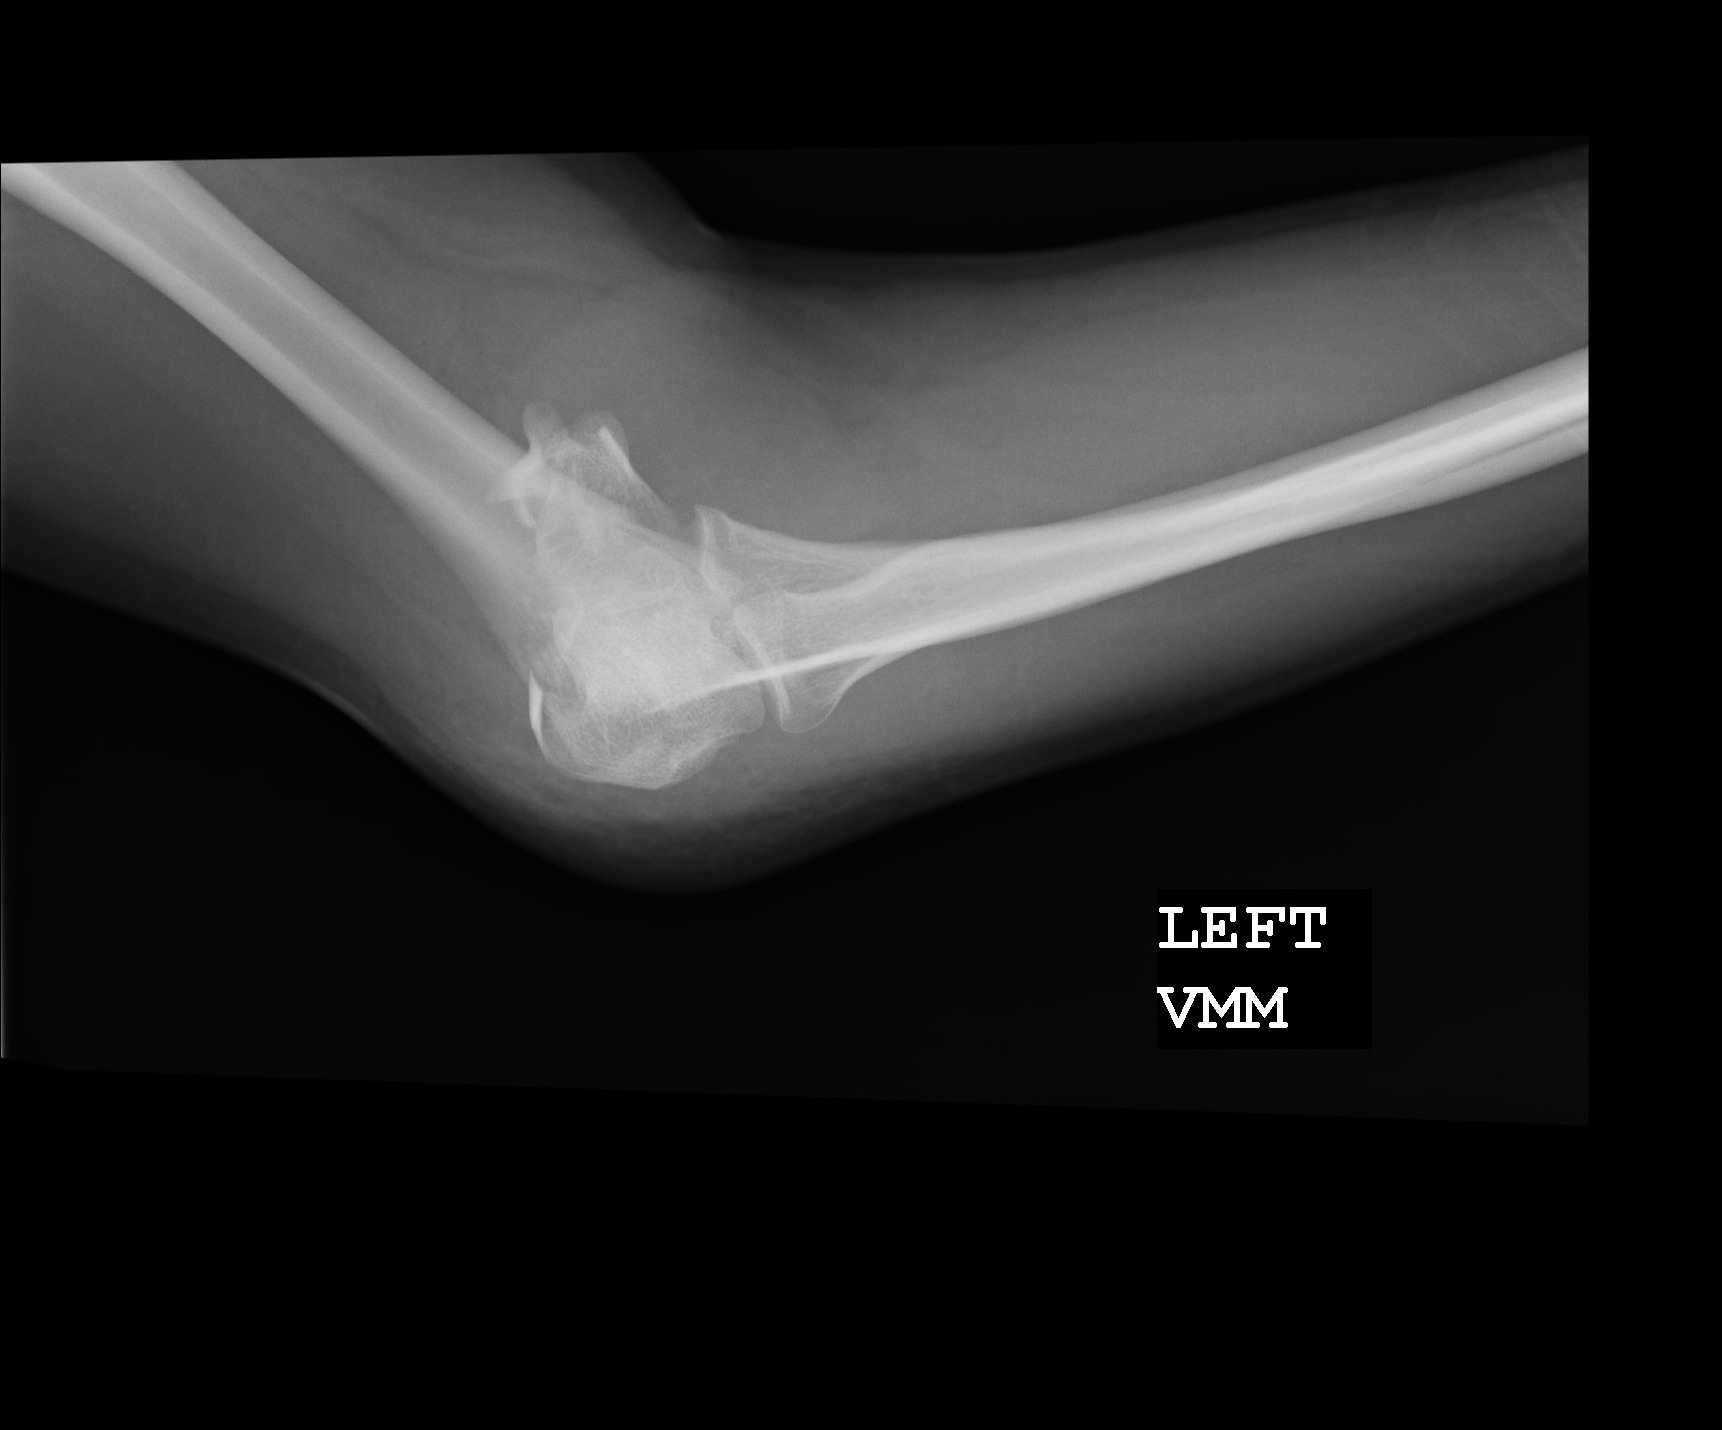

So I had waited six hours before I finally complained twice in quick succession, demanding painkillers, and I was seen by a nurse. Before the painkillers were given I had to endure the torturous procedure of trying to straighten my arms for the x-rays. By now they had seized up into the bent posture that I had taken for the last few hours. It was agony to move them.

The results of the x-rays were conclusive. I had a fracture in each arm, just below the elbows. Double-dosed on painkillers, I floated out to my friend’s car, wearing my slings like a badge of honour as I walked through the waiting room. See, I was injured!